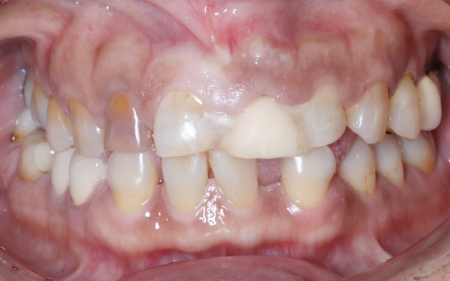

拝見したところ、右上前歯2本(中切歯/1番、側切歯/2番)の根の周りに炎症が認められ、痛みの原因になっていました。

しかし今回の患者様の場合、前歯のすり減りが激しく噛み合わせが低くなっていたため、このままの状態で治療を進めると被せ物を装着した歯が下の前歯に強く当たり過ぎて、被せ物や土台、歯の根も割れてしまう恐れがあります。

また、全体的に歯の着色も見られ、詳しく調べてみたところ、歯の形成期にテトラサイクリン系の抗生物質を大量に服用したことが原因で歯が変色してしまう「テトラサイクリン歯」であることもわかりました。